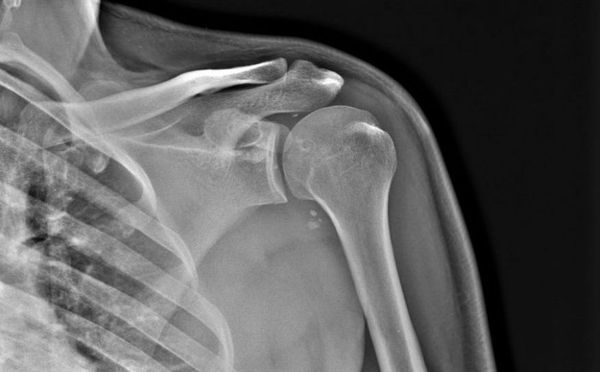

- рентгенография – самый популярный и доступный метод исследования пораженного сустава, но не всегда самый информативный. Уже сформировавшуюся суставную мышь среднестатистических размеров на рентгенологическом снимке видно очень четко, но участок начинающегося некроза выявляют не всегда, так как он может быть небольшим. Поэтому отсутствие изменений на снимке не является основанием для исключения данной патологии;

- первая – появляются дискомфорт и неопределенные несущественные болевые ощущения без какой-либо четкой локализации, нередко они проявляются в виде дискомфорта. На рентгенограмме плечевого сустава обнаруживают овальное тело, состоящее из мертвых тканей, которое отделено полоской просветления от здоровых участков кости;

- 2 стадия– появляются признаки синовита (воспалительного поражения синовиальной оболочки, которая выстилает суставную полость изнутри), также ощущаются умеренные боли в суставе. На рентгеновских снимках определяется более широкая полоса просветления;

- 3 стадия– во время нее определяются уже существенные нарушения, а на рентгенологическом снимке выявляется участок некроза, который частично отделился от кости. Данная стадия представлена полноценной клинической картиной (в том числе блокадами), о которой будет сказано ниже;

- 4 стадия– явления синовита усиливаются, на рентгенологических снимках обнаруживается полностью отделившееся, автономное внутрисуставное тело. Болевой синдром становится более выразительным, но блокады – более редкими, последнее объясняется тем, что суставная мышь может крошиться, из-за чего она уменьшается в размерах.